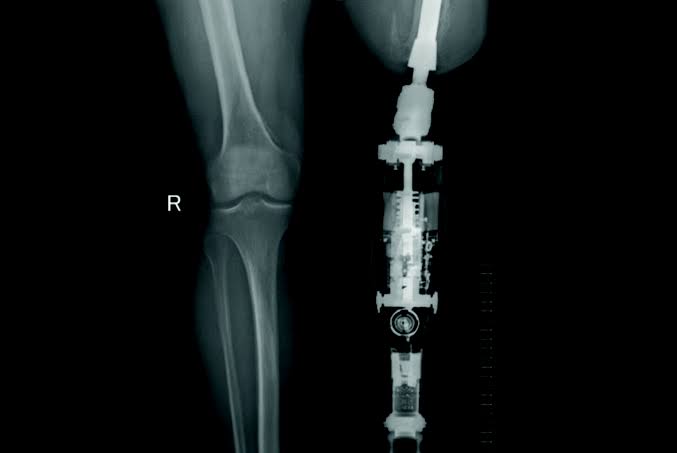

Osseointegration

Artificial Limbs & Appliances staff have been a part of Osseointegration for amputees since 2011. Staff are well versed in the treatment and clinical management of Osseointegration amputees.

Osseointegration is the surgical implant of an “endo-prosthesis” directly into the patient’s bone.

The implant protrudes through the skin and allows for the direct attachment of prosthetic componentry without the requirement of a prosthetic socket. It may be utilised by upper and lower limb amputees.